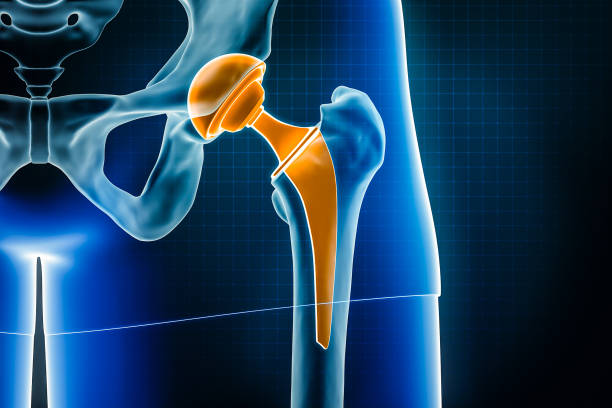

고관절 충돌 증후군

고관절 충돌 증후군은 엉덩이 통증의 주요한 원인 중 하나입니다. 이 질환은 골반 뼈와 대퇴골 사이에서 발생하는 충돌에 의해 2 관절 사이의 연골이 손상되는 질환입니다. 고관절의 구조적인 문제나 잘못된 자세, 과도한 스트레칭 등으로 발생할 수 있습니다.